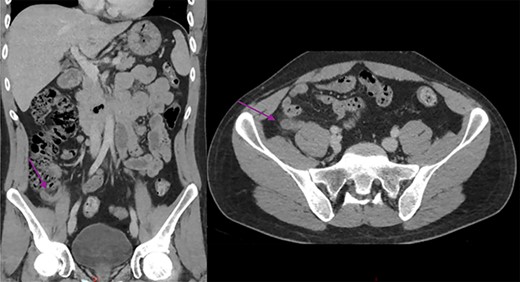

A 30-year-old Aboriginal Australian man with no past medical history presented to the emergency department with a 1-day history of lower abdominal pain. Haemodynamics were within normal range, and on examination the patient had tenderness and guarding in the right iliac fossa. Testicular exam, Rovsing and psoas signs were all negative. Blood tests revealed a mildly elevated C-reactive protein and white cells at 21.9 mg/l (0–8.0) and 11.55 × 109 (4.00–11.00), respectively. Electrolytes, renal and liver function tests were all unremarkable. He proceeded to have a CT scan of the abdomen and pelvis revealing a dilated, thickened appendix with periappendiceal fat stranding. The CT also revealed uncomplicated cholelithiasis, with no other abnormalities in the bowel, adrenals, kidneys, liver, spleen or lymph nodes (Fig. 1).

Abdominal CT scan showing a dilated and thickened appendix with periappendiceal fat stranding (arrow); coronal and axial view.